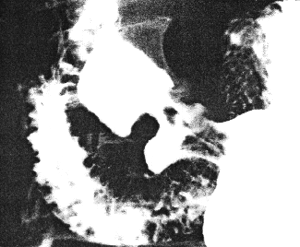

She then presented with a recurrence of symptoms. Endoscopy showed pyloric deformity. Radiographic examination three weeks later revealed an ulcer on the lesser curvature of the pyloric sphincteric cylinder, on the immediate oral side of the ring, with a fistulous communication between the ulcer and the superior fornix of the duodenal bulb (Fig. 31.3). Prominent, permanent circular mucosal folds were present in the cylinder, which remained partially expanded throughout the examination with complete absence of cyclical contraction and relaxation. Repeat endoscopy the following week confirmed the presence of a prepyloric ulcer with a pyloro-duodenal fistula.

![]() |

| Fig. 31.3. Case S.D. Ulcer lesser curvature side of sphincteric cylinder with fistula (arrow) to base of duodenal bulb. Partial expansion of cylinder. Permanent, circular mucosal folds in cylinder |